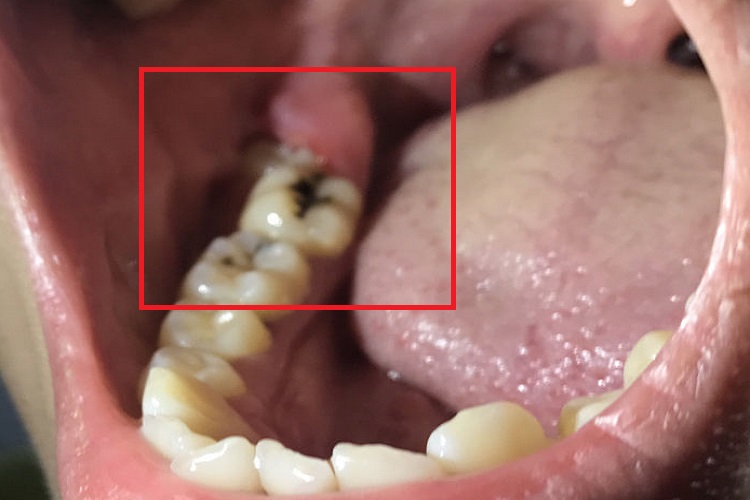

慢性冠周炎患者局部可出现黑斑,大小不等,形状并不规则,表面颜色可逐渐加深。

慢性冠周炎患者牙齿局部可出现大小不等的黑斑,形状不规则,表面颜色可不断加深,周围牙龈发红、肿胀,自觉有疼痛,并伴有口臭、舌苔变厚等症状。

慢性冠周炎主要由于牙齿在萌出过程中,萌出不全以及阻生时,牙冠周围软组织发生炎症导致。

慢性冠周炎以祛除病因为主,可消除盲袋或拔牙。急性炎症消退后,根据患牙具体情况,进行龈盲袋切除或拔牙术。垂直阻生牙萌出后,若与对颌牙能够建立较好的咬合关系,可切除覆盖牙冠的龈瓣以助其正常萌出。若预计施行龈瓣切除术也不能消除盲袋,则应拔除病灶牙。患者需根据自身情况,遵医嘱进行相应的治疗。